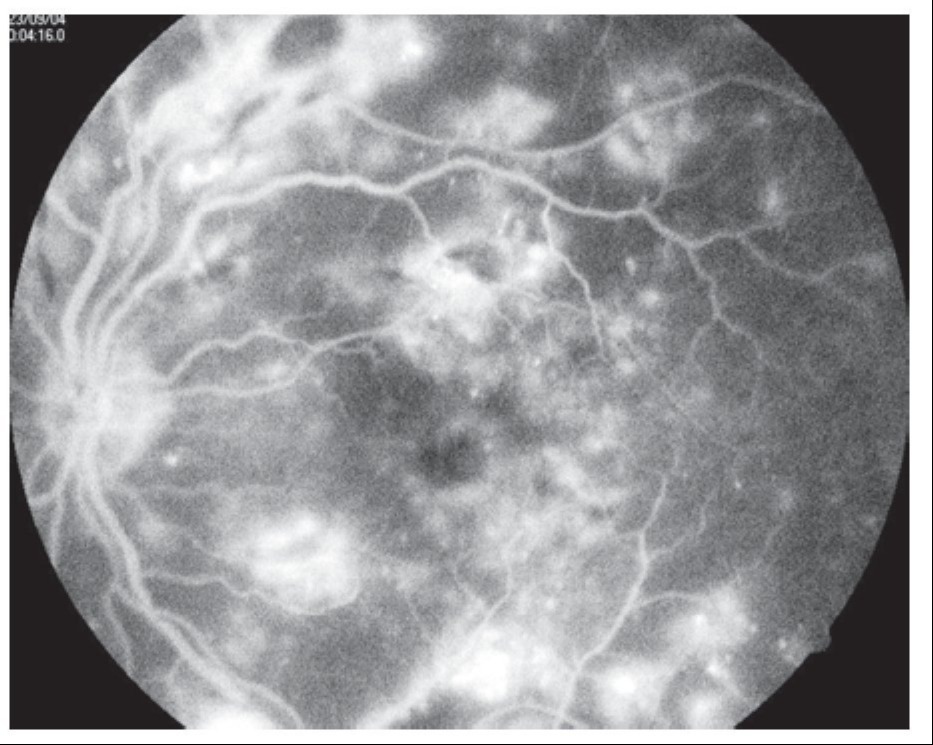

Fluorangiografía

Edema macular diabético